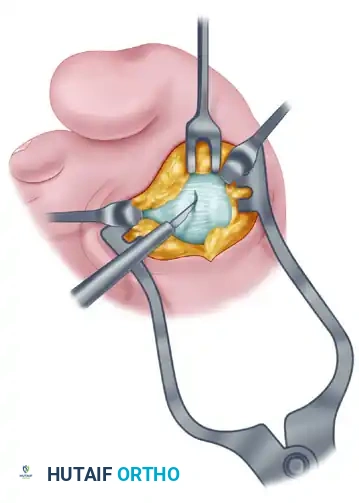

Fibular (Lateral) Sesamoidectomy: Dorsal Approach

In the modern Modified McBride procedure, the fibular sesamoid is rarely excised. However, if a severe, rigid valgus deformity persists after a complete adductor release and lateral capsulotomy, and the sesamoid cannot be mobilized, a fibular sesamoidectomy may be indicated.

- Adequately separate the first and second metatarsal heads using a lamina spreader or Inge retractor.

- Plantarflex the MTP joint 10 to 20 degrees to reduce tension on the sesamoid apparatus.

- Grasp the fibular sesamoid firmly with a small Kocher clamp or sturdy tissue forceps, pulling it laterally into the intermetatarsal space.

- Carefully release the intersesamoid ligament. Once incised, the fibular sesamoid can be delivered into the intermetatarsal space for straightforward removal.

- Surgical Warning: Extreme care must be taken when incising the intersesamoid ligament to avoid severing the flexor hallucis longus (FHL) tendon, which lies immediately plantar to it. If the FHL is inadvertently severed at this level, it generally should not be repaired, as repair often results in a rigid, fixed flexion contracture of the interphalangeal joint, whereas loss of the tendon causes minimal functional impairment.

- Alternative to Excision: Release part or all of the FHB lateral head at its insertion into the fibular sesamoid. Remember, performing both a metatarsal osteotomy and a fibular sesamoidectomy drastically increases the risk of iatrogenic hallux varus.